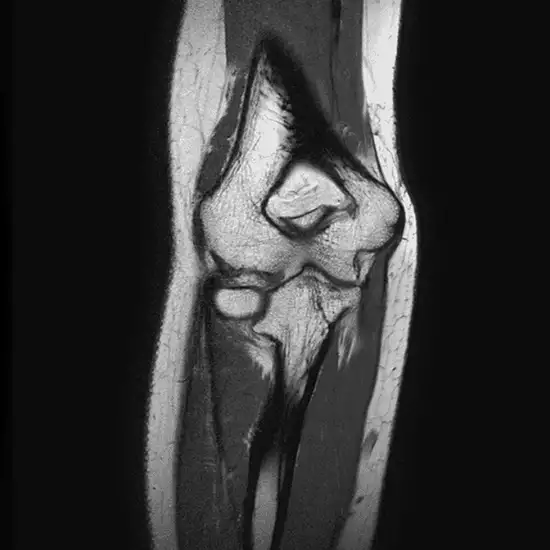

The bones of the left elbow joint and the soft tissues, including the cartilage, tendons, ligaments, muscles, and blood vessels, are visible on an MRI of the elbow joint.

The doctor orders this test to identify any fractures in the bones that make up the elbow joint and any infections or unusual bone growth.